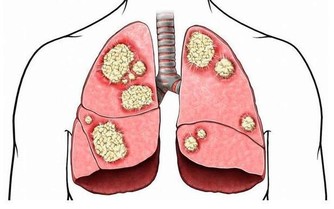

1、會加快前列腺癌的生長速度,會引發腎衰竭脂類的腎臟疾病。